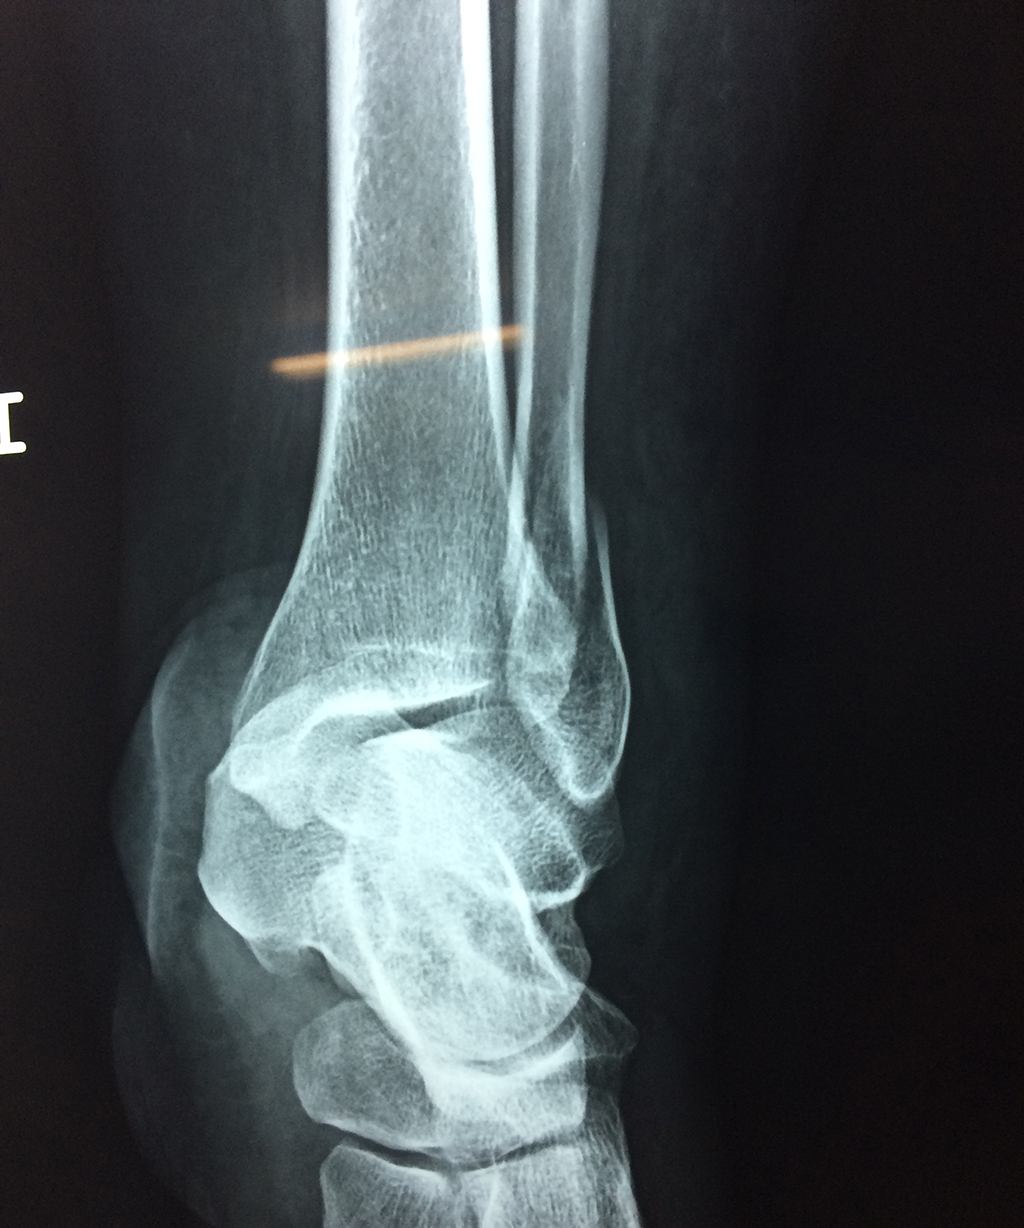

Una fractura de tobillo es la rotura de uno o más de los huesos del tobillo. Estas fracturas pueden ser:

- Parciales (el hueso está sólo parcialmente fisurado, no del todo).

- Completas (el hueso está perforado y está en 2 partes).

- Producirse en uno o ambos lados del tobillo.

Algunas fracturas de tobillo pueden requerir cirugía si:

- Los extremos de los huesos están desalineados entre sí (desplazados).

- La fractura se extiende hasta la articulación del tobillo (fractura intra-articular).

- Los tendones o ligamentos (tejidos que sujetan los músculos y los huesos entre sí) están rotos.